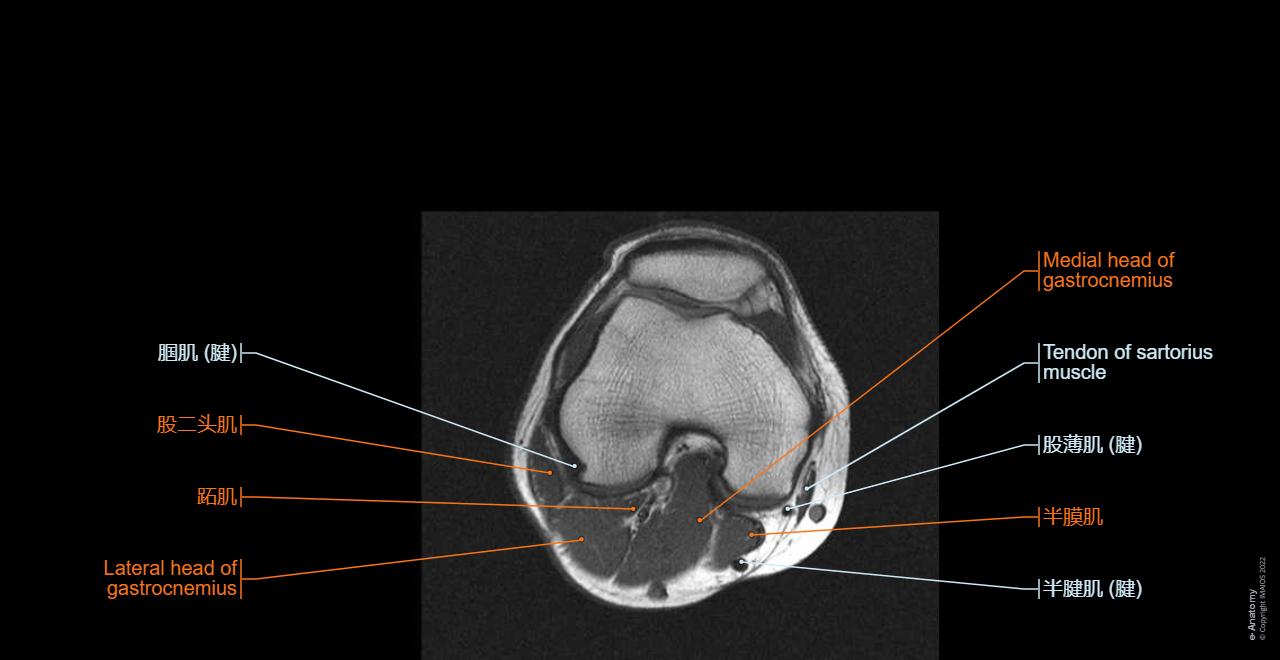

膝关节3D MRI成像

3D膝关节MRI体积数据

数据集的构建与核心内容

7,970

3D膝关节MRI体积

• 来源于NIH资助的OAI纵向研究项目 [2]

• 精选DESS序列,高分辨率体素数据

• 覆盖基线到48个月随访多个时间点

3D MRI体积 I 输入的原始三维膝关节MRI影像数据 包含T1、T2加权像的膝关节MRI扫描